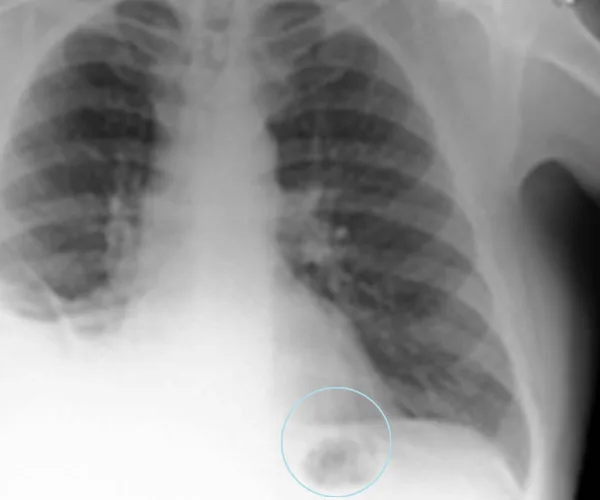

The patient was given a chest X-ray which produced a frightening result. A dark mass appeared over one of his lungs which doctors initially thought, based on the fact that the patient had been a long-term smoker, was lung cancer.

A man was rushed to hospital for tests when an X-ray presented a dark mass on his lung (Picture: BMJ Case Reports).

However, after further tests, it was discovered that the dark mass was not a tumour, in fact, it was a plastic toy traffic cone that had lodged itself in the man’s lung.